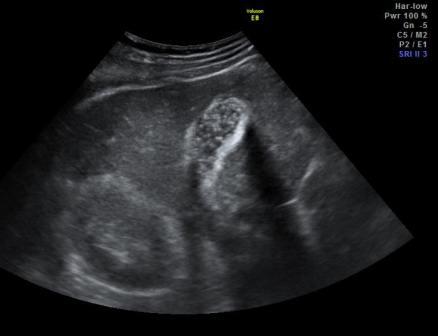

Заголовок сообщения: Содержимое двух ЖП.

Вот два пациента с обострением холецистита. Смотрите сами...

эмпиемка?

В первом случае клиника более менее была. Во втором всё тихо. Чем всё завершилось не знаю. Но в первом случае на "эмпиемку" похоже.